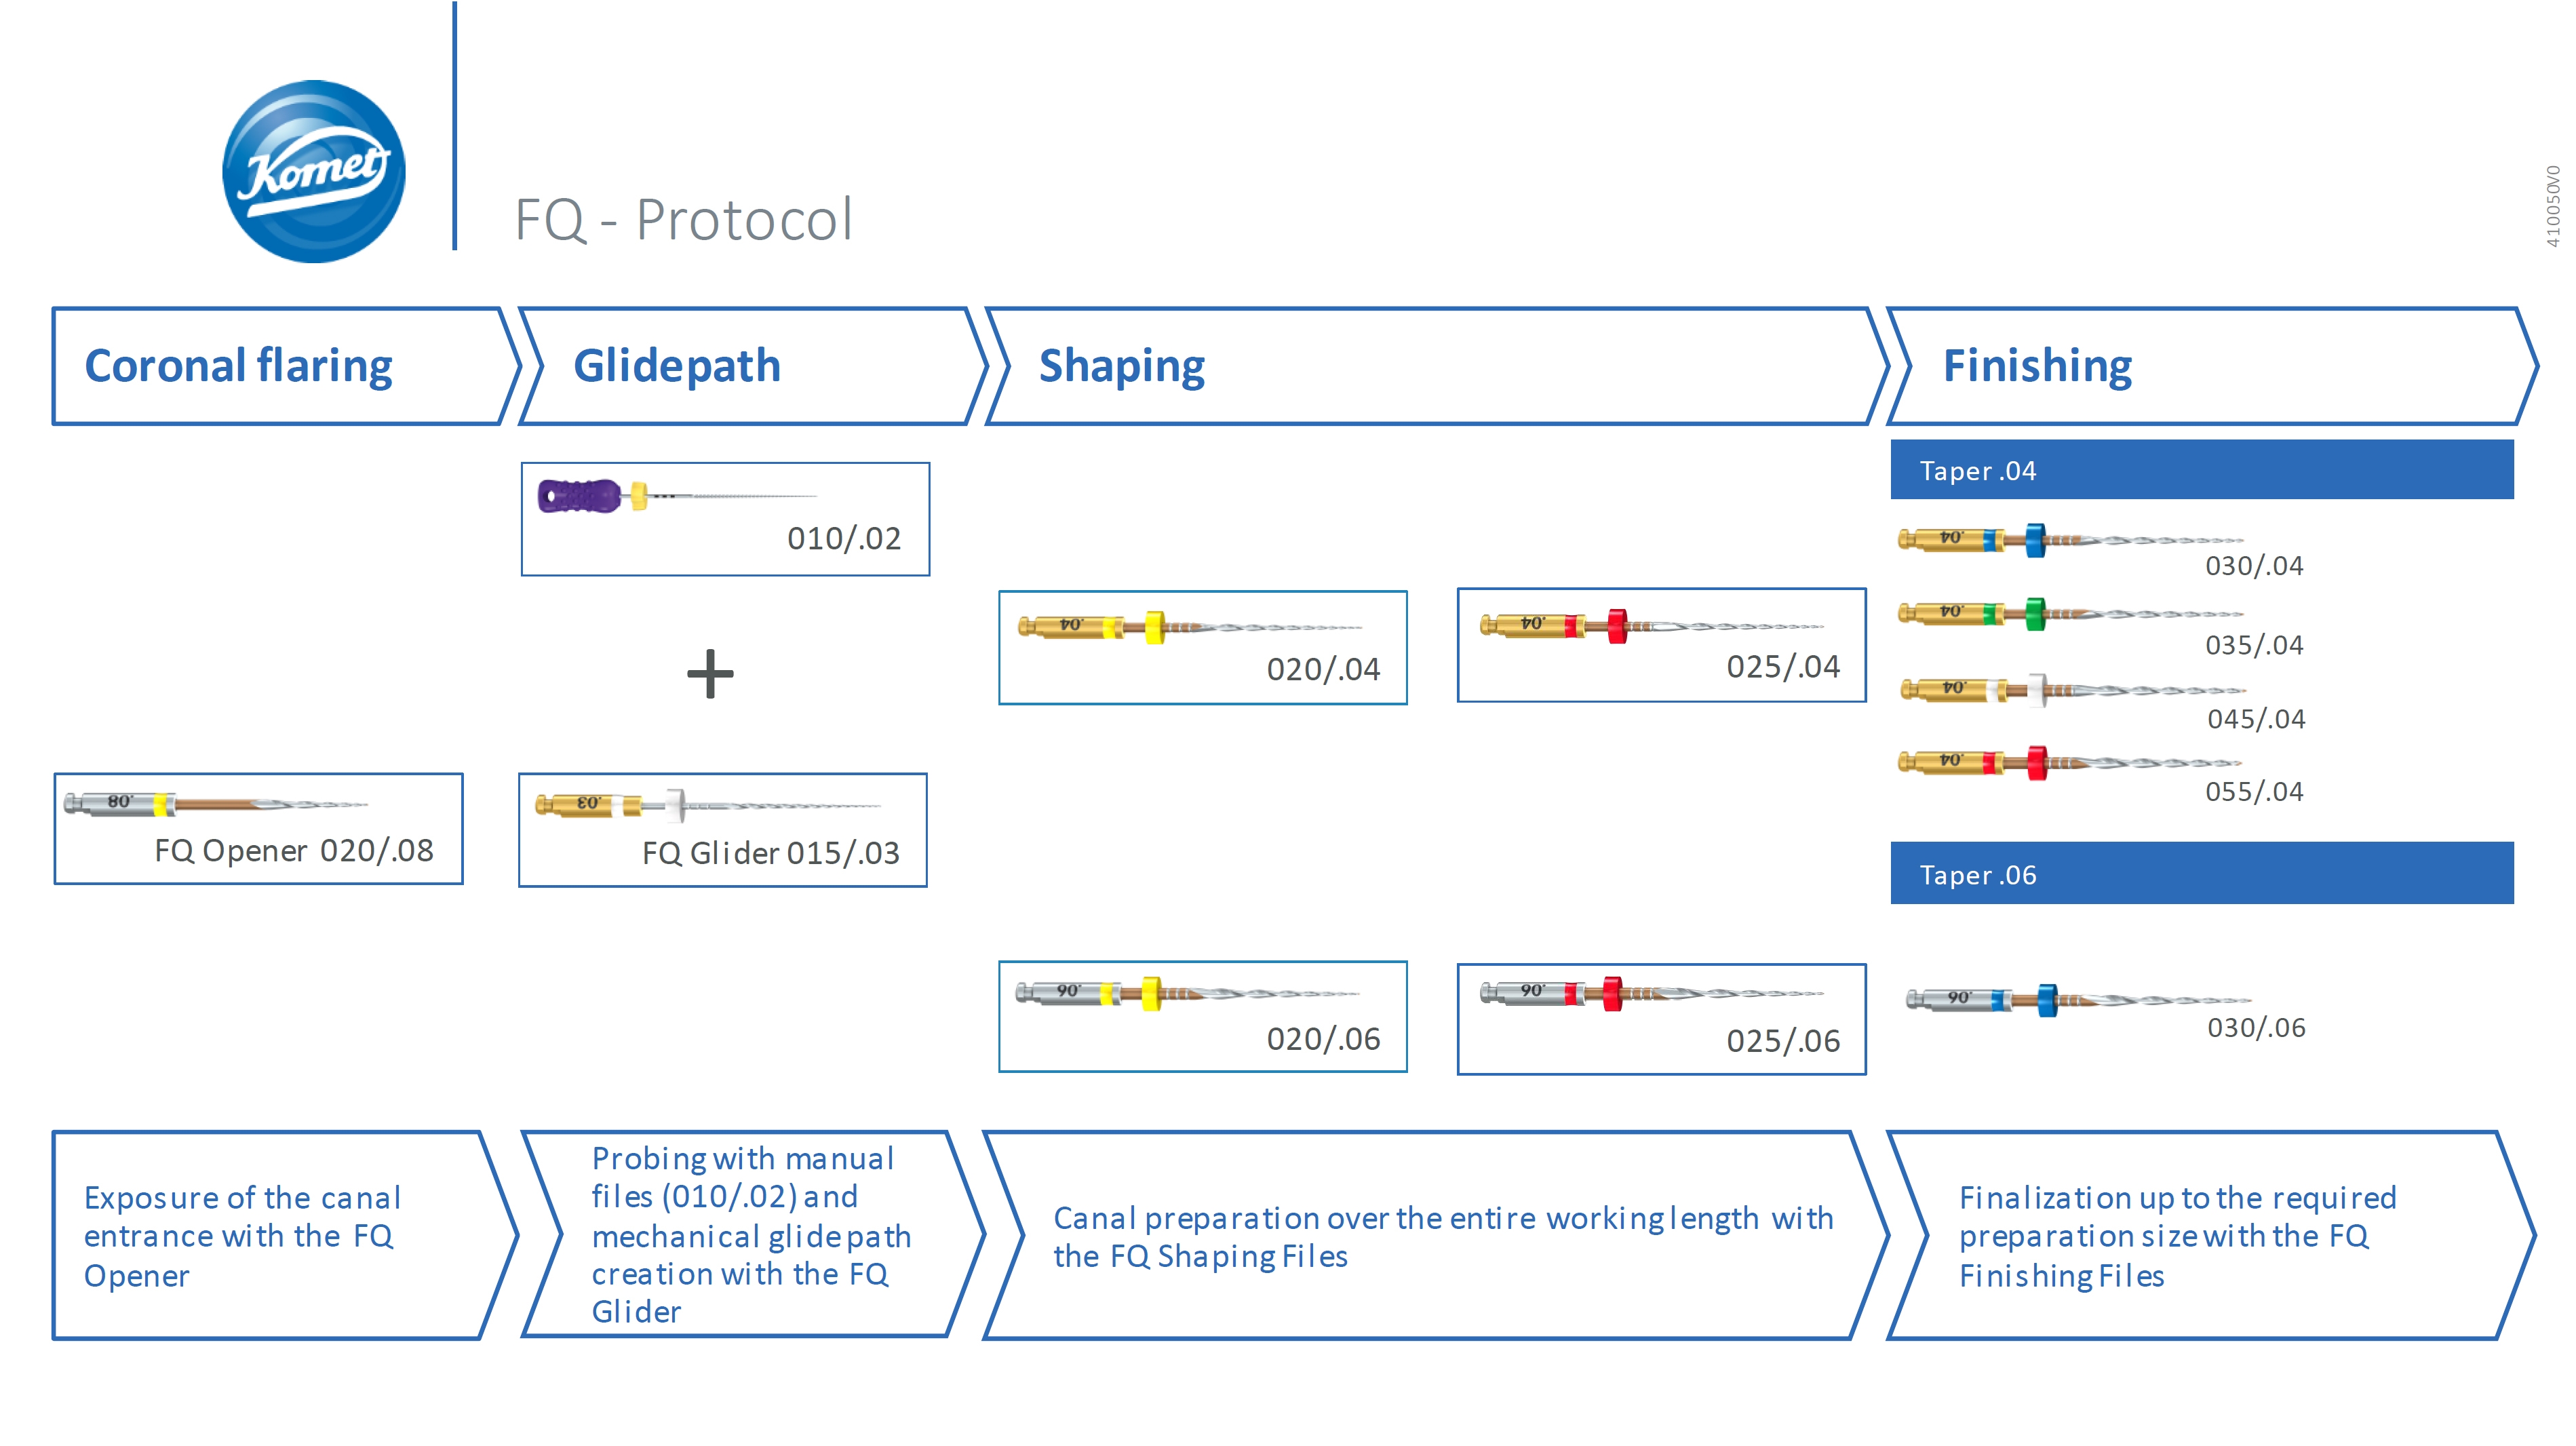

Vista la forma anomala e la dimensione ridotta della radice accessoria, dopo i passaggi con Komet Skytaper 15/03 e 20/03, il Dr. Natalini riesce ad arrivare senza forzare, come ultimo passaggio, con un FQ 25/04 a 2 mm dall’apice, la cui rifinitura, viene completata manualmente sempre con un file 25.

Trattamento endodontico di un incisivo laterale superiore con due radici - parte 10Vista la forma anomala e la dimensione ridotta della radice accessoria, dopo i passaggi con Komet Skytaper 15/03 e 20/03, il Dr. Natalini riesce ad arrivare senza forzare, come ultimo passaggio, con un FQ 25/04 a 2 mm dall’apice, la cui rifinitura, viene completata manualmente sempre con un file 25.